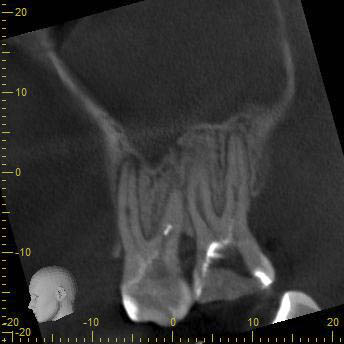

BN2627_DVT (5 von 17) Veröffentlicht 1. Dezember 2014 am 344 × 344 in Unerwartete Anatomie Zahn 26, 27- die WF